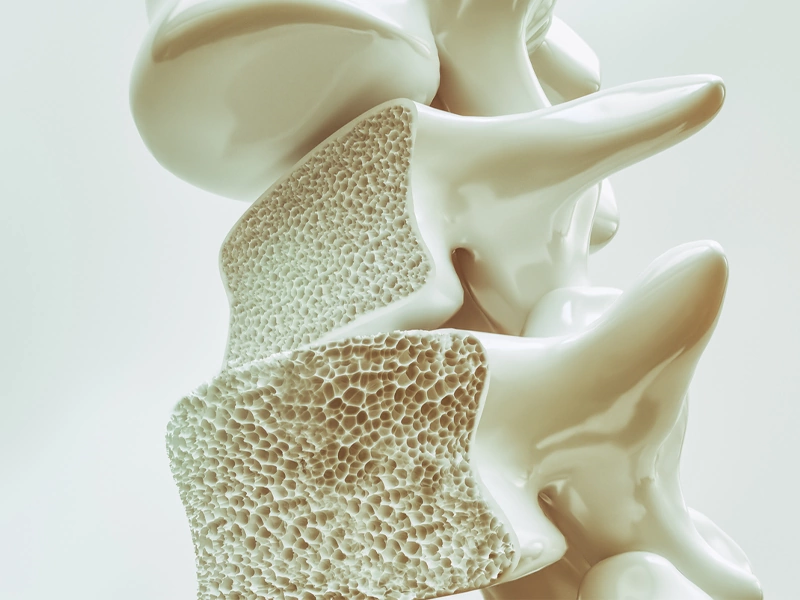

پوکی استخوان را شکست دهید

پوکی استخوان یک اختلال اسکلتی است که بیشتر در سنین بالا بروز میکند و ویژگی آن کاهش استحکام استخوان هاست. این بیماری به تدریج و